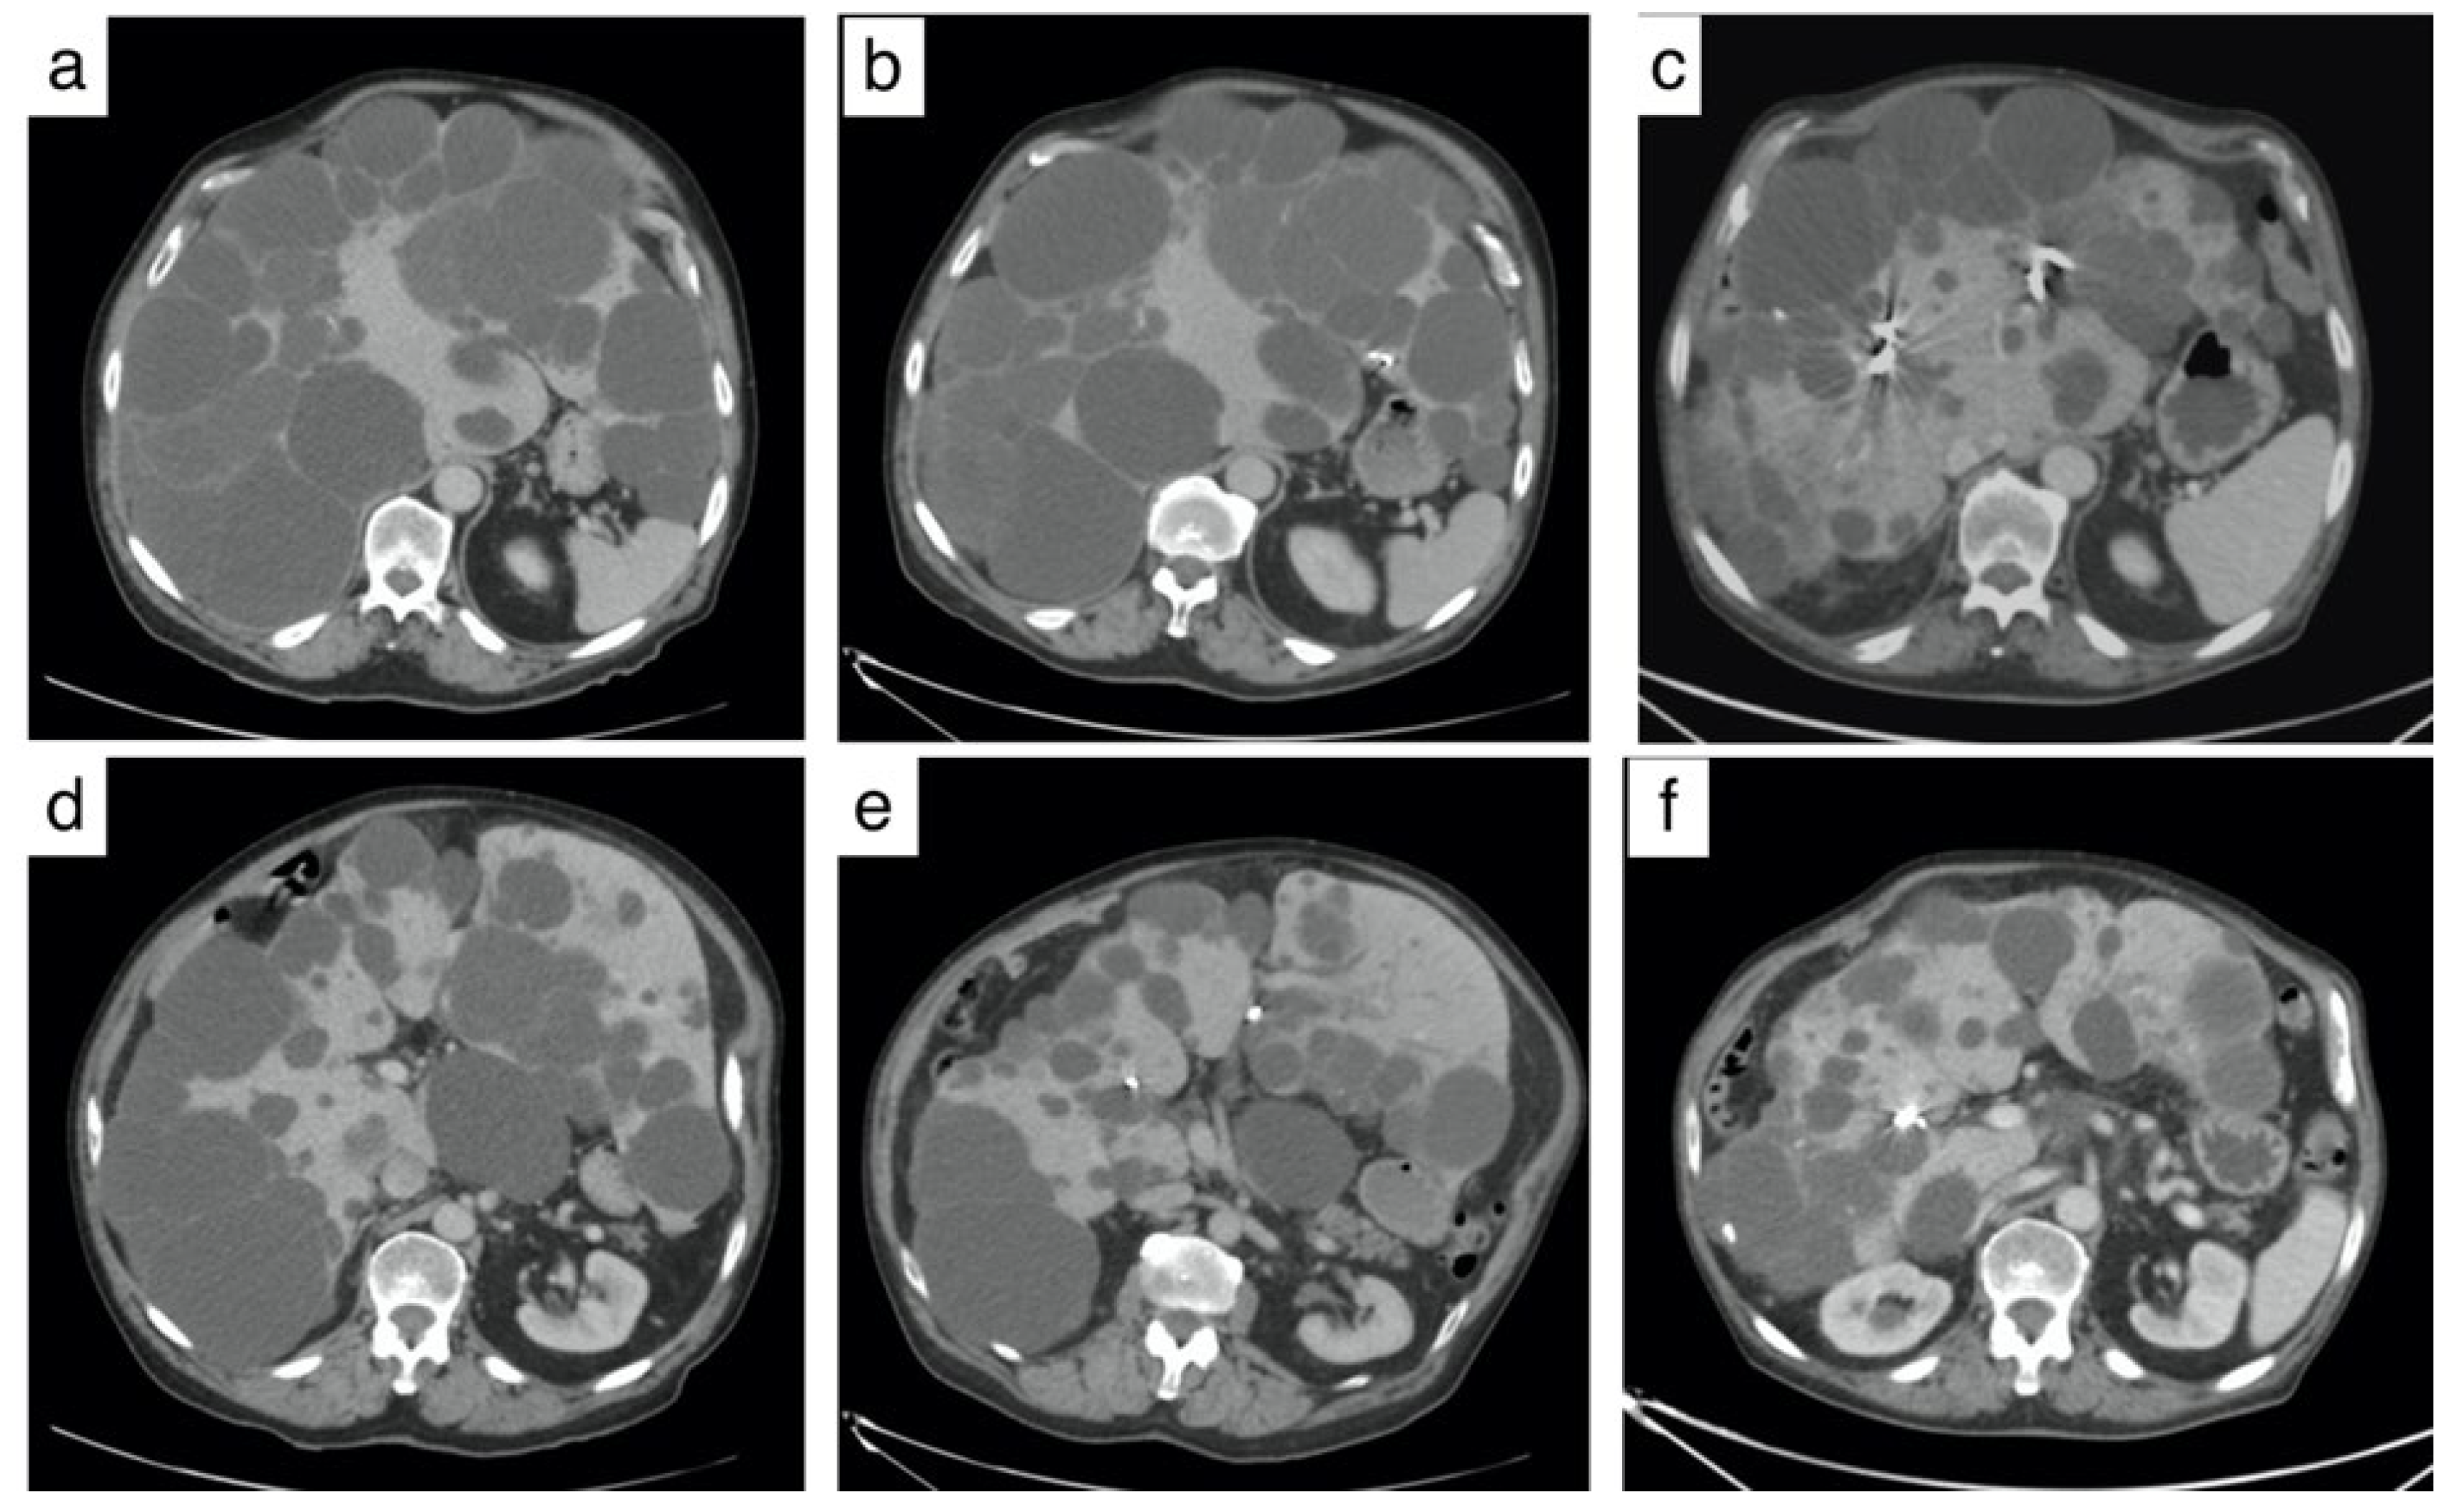

3.4. Reduction in Hepatic Volume (Figure 2 and Table 3)